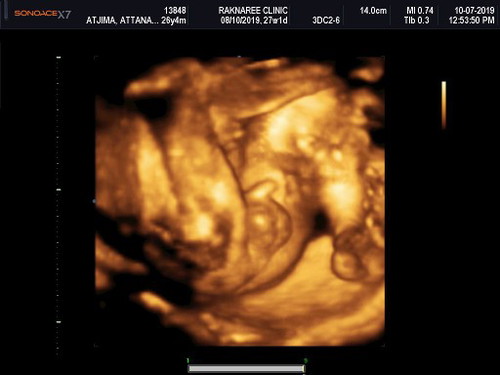

กลัวแม่ไม่รู้ว่านู๋เป็นผู้ชาย

นอนไขว่ห้างสบายใจจังเลยครับ❤❤

ซาวแบบ4มิติ เหนหน้าชัดๆเลยคะ

เอ็นดูท่านอน หนูนอนท่านี้ได้ด้วยเหรอ แต่เปิดเผยจังเลยครับ

อุ้ยจู๋ๆๆๆ..ถ่าโชว์จู๋น่ารักค่ะแม่ยินดีด้วยน่ะค่ะ